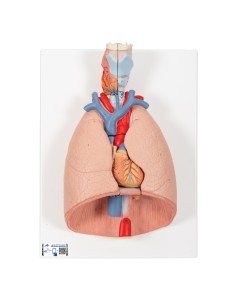

Dal cranio in 22 parti con incastri magnetici ai modelli di colonna vertebrale, da quelli di articolazioni a quelli di cuore, ogni pezzo della nostra collezione è progettato per un’immersione totale nello studio dell’anatomia umana. I nostri modelli, realizzati tramite scansioni di ossa vere, garantiscono un’esperienza tattile autentica e una fedeltà di peso quasi identica agli originali.

Essenziali per studenti e professionisti, i nostri modelli anatomici sono strumenti didattici che permettono di osservare le strutture anatomiche con precisione, eliminando la necessità di dissezioni o studi invasivi. Sono inoltre utili per spiegare ai pazienti le patologie, rendendo la comunicazione più efficace e risparmiando tempo prezioso.